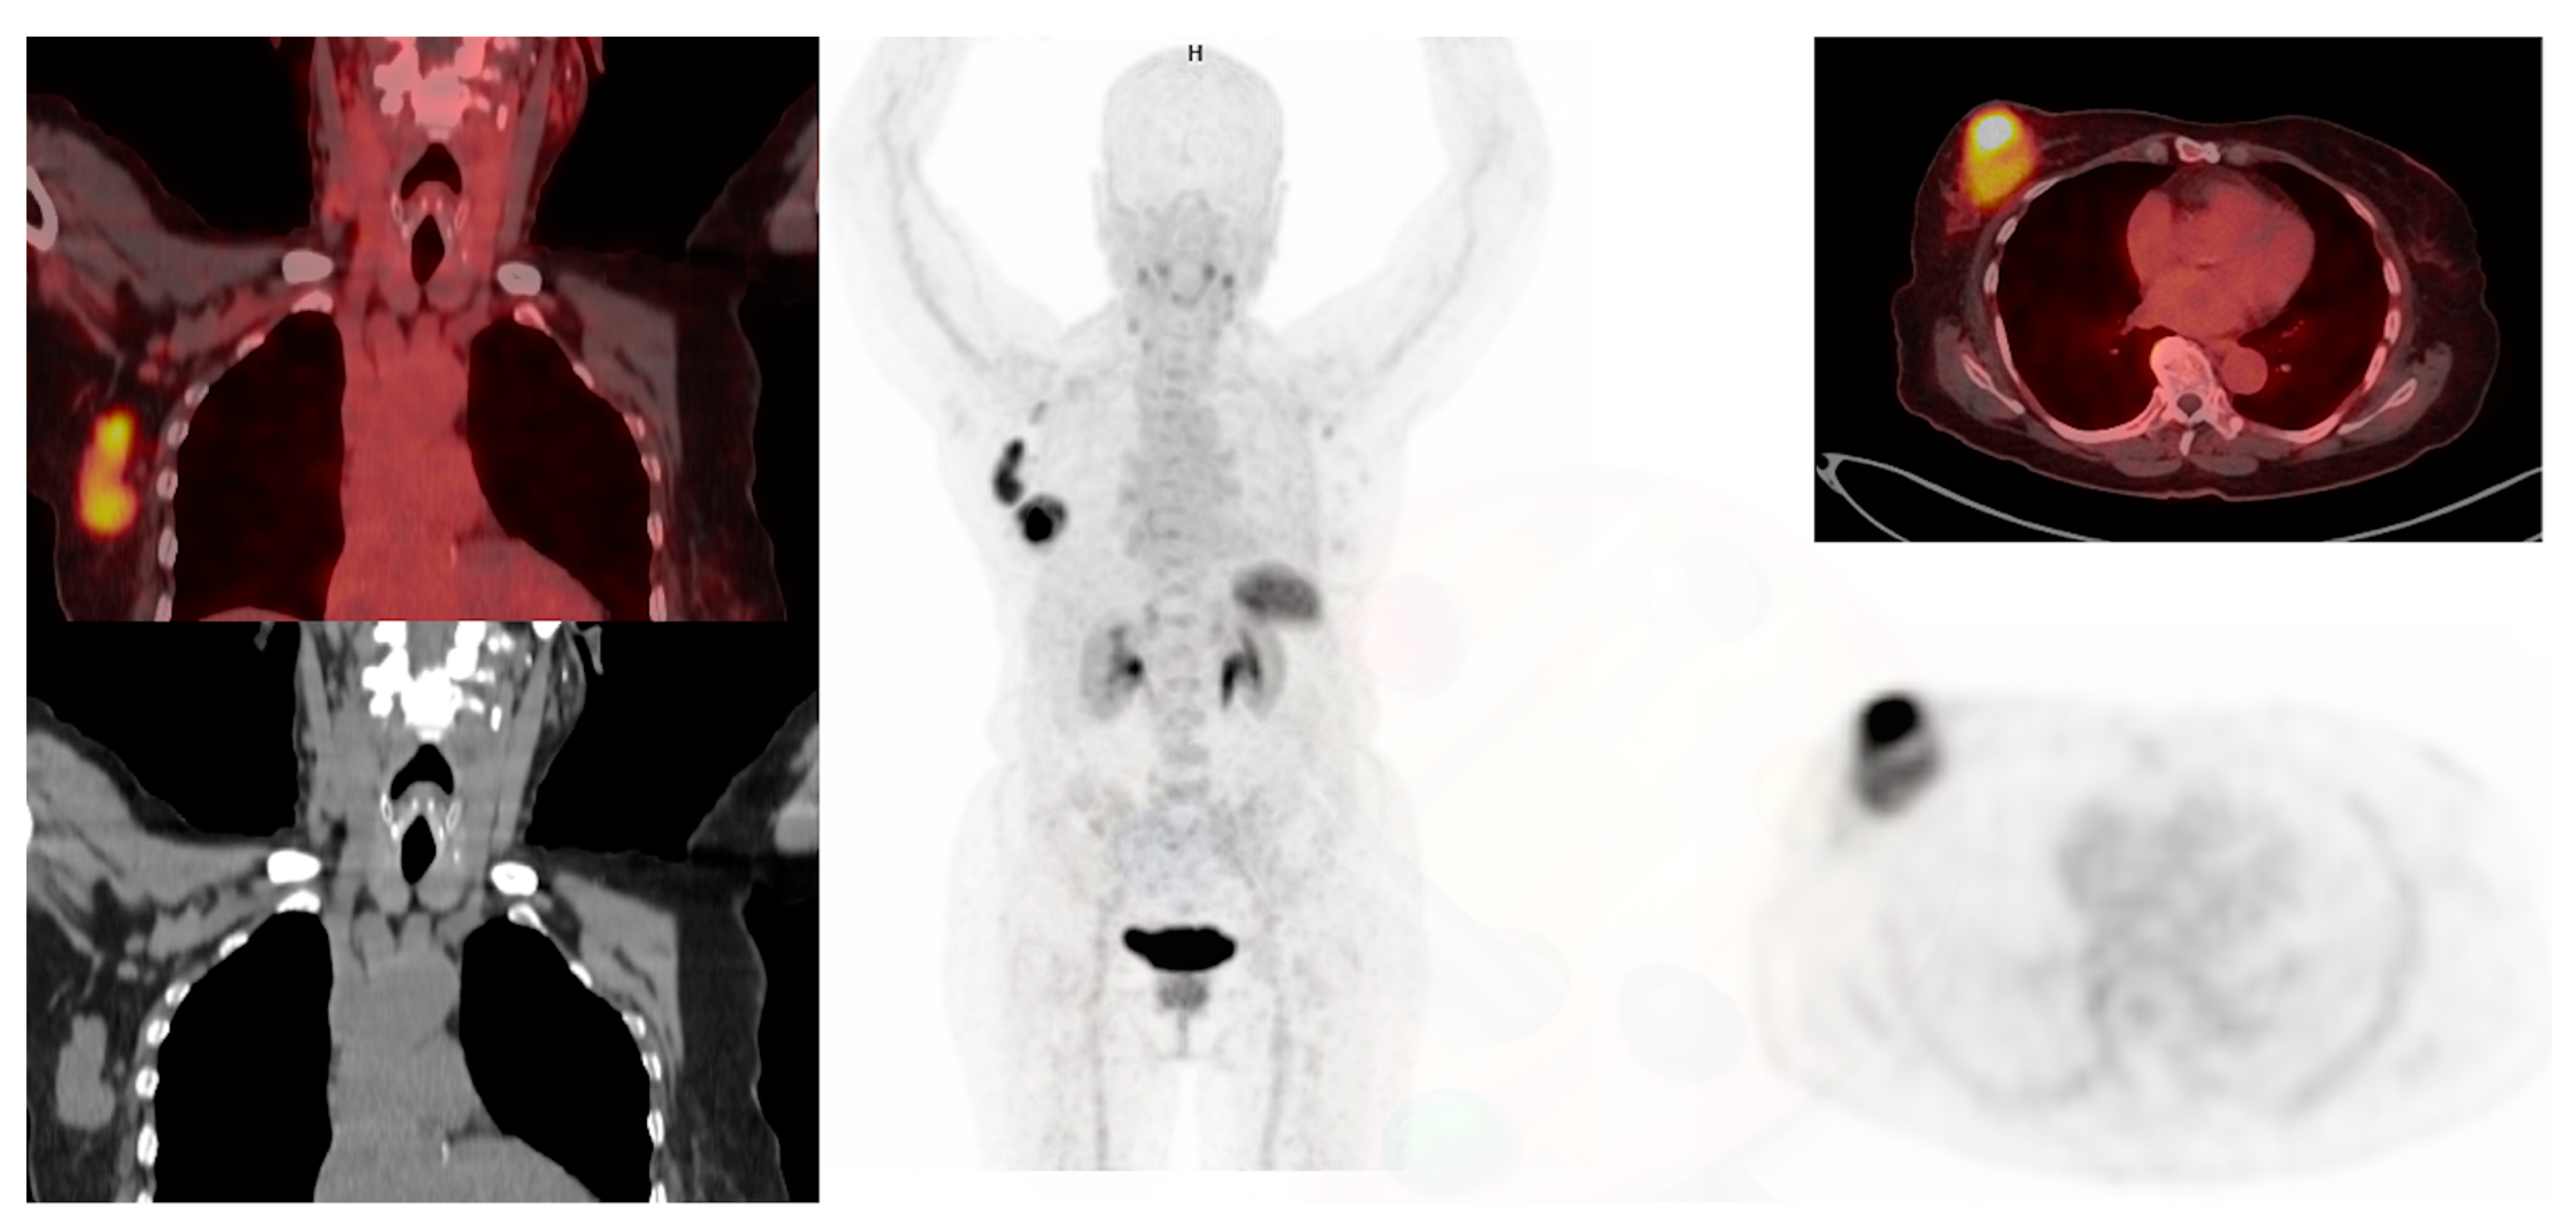

3.4. Estrogen Receptor Imaging

3.5. Progesterone Receptor Imaging